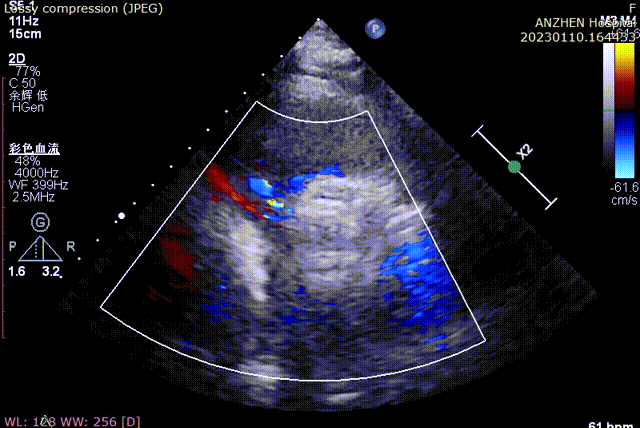

术前超声

术后超声